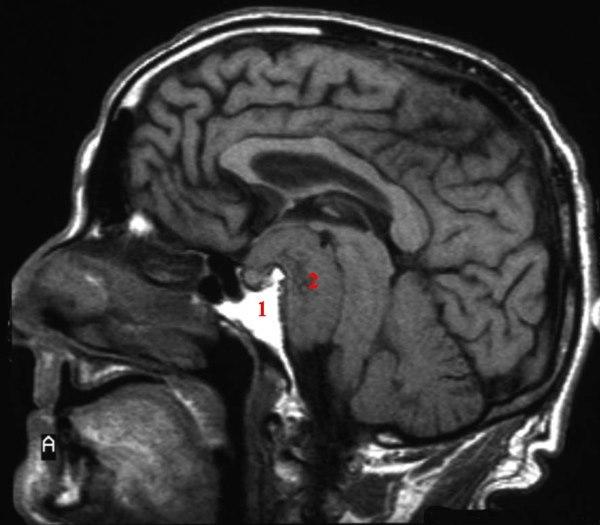

MR uten kontrast - saggitalsnitt

1. Meningeomet (svulst utgående fra hjernehinner)

2. Ødem